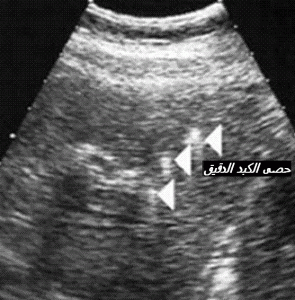

5- تشخيص حصى دقيق لامع داخل الكبد مصحوبا بظل في خلفه ( ذنب الكوميت) (27)

omete microlith hepatique

متعلق بهبوط البلار الكوليستيرولي داخل القنوات الصفراوية . أما الفحوص الكبدية فكثيرا ما تظل قليلة الاضطراب ( ارتفاع متوسط لفحص جاما ج ت)باستثناء حالة الأنجيوكوليت . و يحتمل أن يمسي تشخيص ظل الكوميت أمرا عسيرا خاصة بسبب تووفر غزارة الغازات في السائل الصفراوي (28)و خاصة ان الفحص بالرنين المغنطيسي يعجز عن تشخيص الحصى الدقيق الذي يقل حجمه عن 6 ملم . ليس غريبا أن يضاف لذلك الحصى الكبير الحجم .